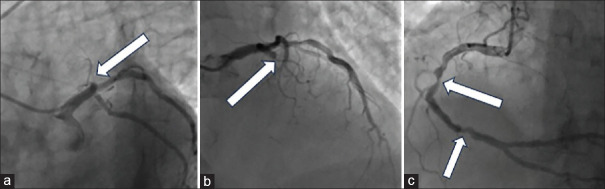

Masquerading bundle branch block (MBBB) is a rare presentation of bifascicular blocks. It is the result of a right bundle branch block associated with an advanced left anterior fascicular block due to extensive damage to the conduction system. We present the case of a 75-year-old male with late onset presentation anterior wall myocardial infarction (MI) with ongoing ischemia (which evolved into a ventricular septal defect [VSD]). Electrocardiographically, the MBBB is characterized by a prominent R in V1, left axis deviation and absence of small S waves in I and aVL. Its presence confers a poor prognosis and high risk of progressing to advanced atrioventricular block (AAVB). A mortality rate between 18% and 38.9% has been found and 41.4%-59% of the patients develop AAVB requiring pacemaker implantation. To our knowledge, this is the first reported MBBB case in the setting of an MI complicated with VSD, demonstrating its association with the presence of critical anteroseptal ischemia. The patient rejected any kind of intervention, palliative care was offered, and he died 2 months later.

伪装束支阻滞(MBBB)是一种罕见的双束状阻滞。它是由于传导系统的广泛损伤而导致的右束支阻滞合并晚期左前束阻滞的结果。我们报告一例75岁男性迟发性前壁心肌梗死(MI)伴持续缺血(演变为室间隔缺损[VSD])。在心电图上,MBBB的特征是V1明显的R,左轴偏移,I和aVL没有小S波。它的存在导致预后不良和进展为晚期房室传导阻滞(AAVB)的高风险。死亡率在18% - 38.9%之间,41.4%-59%的患者发生AAVB,需要植入起搏器。据我们所知,这是第一例心肌梗死合并室间隔缺损的MBBB病例,表明其与严重室间隔缺血存在关联。患者拒绝任何干预,接受姑息治疗,2个月后死亡。